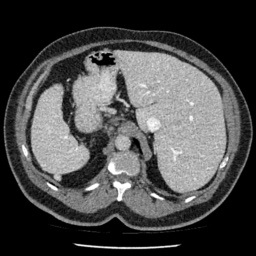

Refer to caption

(e) Normal Liver

(f) Normal Liver

(g) Liver Tumor

(h) Liver Tumor

Figure 4: We show some example brain MRI slices from BratS18 (first row) and Liver CT slices from LiTS (second row). Both normal- and abnormal-looking images are provided.

Aside from the difference in imaging tissue and modality of these two data sets, the tumor regions on the CT images are of different shape and size, as can be seen in Figure 4. Also, many CT scans are acquired in a way that introduces greater noise-like artifacts than MRI. For each dataset, 80%percent8080\% of randomly selected data are used for training and the resting 20%percent2020\% for testing.